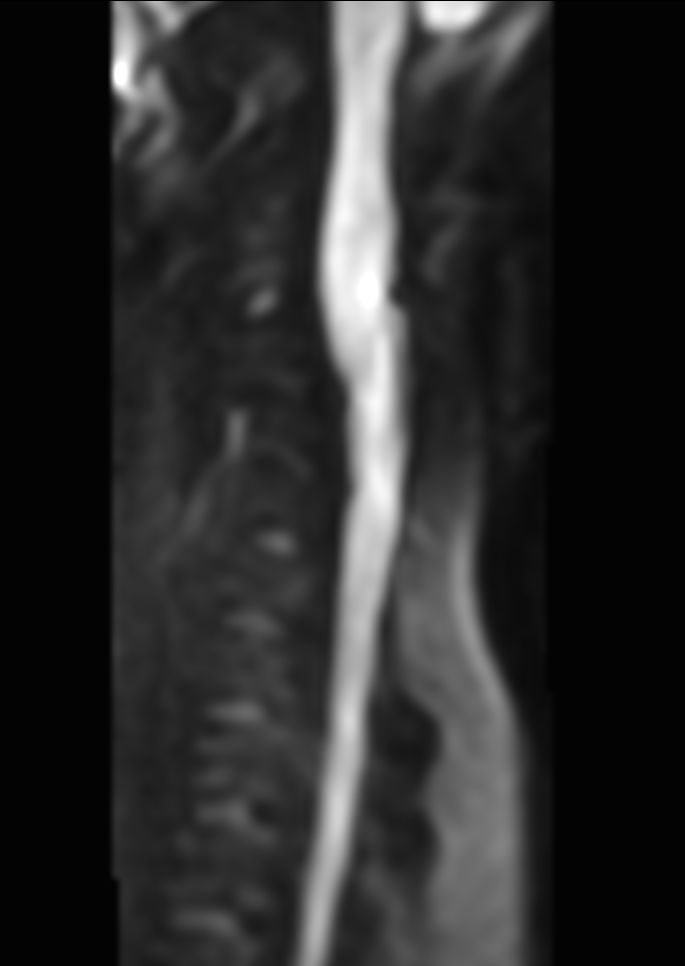

Sagittal Zoom DWI (b1000)